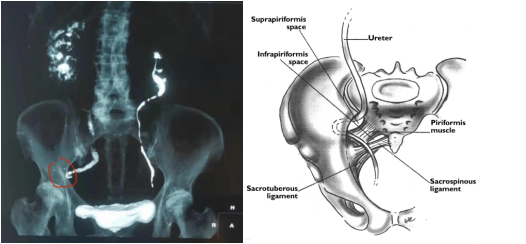

患者刘奶奶前些日子因右腰、右腹部反复疼痛前往医院就诊 , 经检查发现是右侧输尿管向侧方嵌顿入了坐骨大孔 , 行成疝囊 , 被诊断为“输尿管坐骨大孔疝” 。 因为嵌顿时间较长 , 已经导致输尿管梗阻并发肾积水 , 严重影响肾功能 。

(上图红色箭头所指是坐骨大孔术前和修补后 )

坐骨大孔疝是盆底疝的一种 , 盆底疝是指疝囊在骨盆盆缘以下的腹内、外疝 。 从解剖部位及疝内容物可以分为:盆底腹膜疝、会阴疝、闭孔疝和坐骨大孔疝 , 其中坐骨大孔疝最为罕见 。